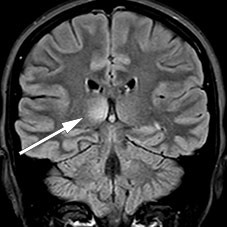

MR caput og MR totalmedulla viste høysignalforandringer i mer enn 50 % av medullas diameter med svak kontrastoppladning ved nivåene C4–C5, C6–C7 og Th11–Th12 (figur 1), men tilbakegang av meningittforandringene. Radiologen mente bildene var best forenlig med akutt disseminert encefalomyelitt. Ny lumbalpunksjon (tabell 1) viste økende celletall og moderat økt totalprotein og albumin forenlig med blod–hjernebarrieresvikt. På bakgrunn av økende celletall i cerebrospinalvæsken ble det igjen gitt aciklovir inntil negativ PCR for herpes simplex-virus forelå.

Kontroll-MR en måned senere viste tilkommet lesjon i høyre thalamus uten kontrastoppladning (figur 2) samt to nye, små lesjoner med kontrastladning i medulla ved C5, C6 og muligens også Th5. De infratentorielle lesjonene hadde gått fullstendig tilbake, og forandringene i medulla oblongata var redusert.